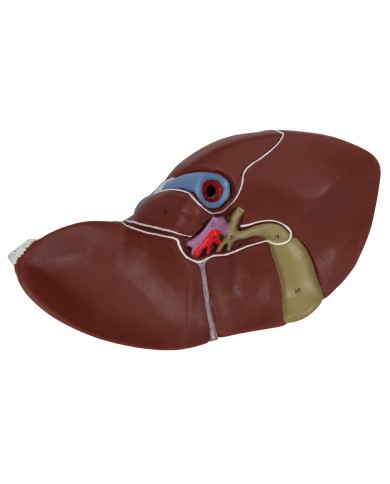

I Modelli anatomici 3B scientific ed Erler Zimmer sono quanto di meglio esista per studiare l'anatomia del corpo umano, il catalogo dei modelli anatomici comprende modelli di cranio, scomponibili, colorati, crani anatomici, crani su cavalletto, e il modello di punta, il cranio in 22 parti, ad incastro magnetico.

Questo e tanto altro ancora trovi nella sezione dedicata ai modellini anatomici, occhi, denti, orecchio, naso e gola, e i modelli anatomici per ostetricia e ginecologia, per lo studio dell'anatomia della pelvi e del bacino umano.

I modelli anatomici didattici sono riproduzioni di strutture anatomiche perfettamente uguali a quelle vere, i modelli di ossa sono realizzati dalla scansione di ossa vere, l'esperienza tattile è assolutamente realistica, ed anche il peso delle ossa corrisponde all'incirca al peso delle ossa vere.

Sono indispensabili per lo studio dell'anatomia umana, oggi è possibile osservare le strutture anatomiche senza la necessità di dissezionare cadaveri o di effettuare studi pericolosi su pazienti vivi.

Gli studenti di medicina utilizzano i modelli anatomici per i loro studi di anatomia umana, studiare l'anatomia sui libri non basta, un modellino anatomico permette uno studio molto più accurato che una foto o un disegno su un libro.

Medici, fisioterapisti, osteopati e professionisti sanitari utilizzano i modelli anatomici per dare spiegazioni ai pazienti sulle patologie, risparmiando tanto tempo prezioso durante la spiegazione, che diventa molto più efficace.